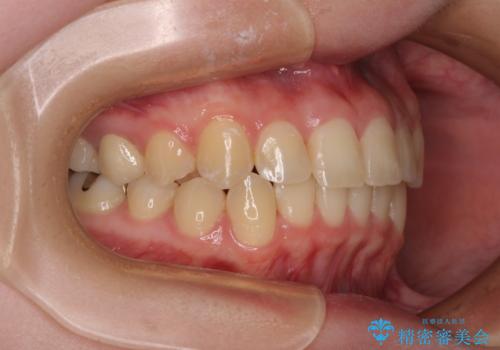

前歯のクロスバイト ギラギラのワイヤー装置で矯正治療

- 前歯のクロスバイトを改善したいとのことで来院された患者様です。

マウスピース矯正では前歯の神経への負担が大きいことを懸念され、ワイヤー装置による矯正治療を行うこととしました。

クロスバイトが改善する際は、前歯しか接触しないため、痛みがあったり食事が取りにくかったりと、不便な時期がありますが、1年強の短期間で無事に治療を終えることができました。